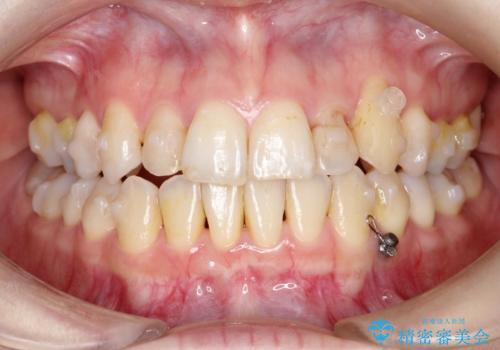

- 左上の八重歯の改善を希望され来院された患者様です。

初診時の歯並びの状態としては、上下ともに前歯部中心としたの中等度のがたつき(叢生)があり、全特に左上の前歯は1本だけ引っ込んでおり、犬歯は外に飛び出した状態でした。

抜歯は行わず上顎の奥のスペースを利用して歯をスライドする方法の他に歯列弓の拡大やディスキング(歯と歯の間の隙間を作る処置)を行い叢生を改善しましています。

歯の大きさの不揃いが原因の正中のズレは、ディスキング量を調整することで合わせました。

矯正装置としてはマウスピースを使用しています。

見た目、嚙み合わせ及び、治療期間や施術内容に大変ご満足いただきました。